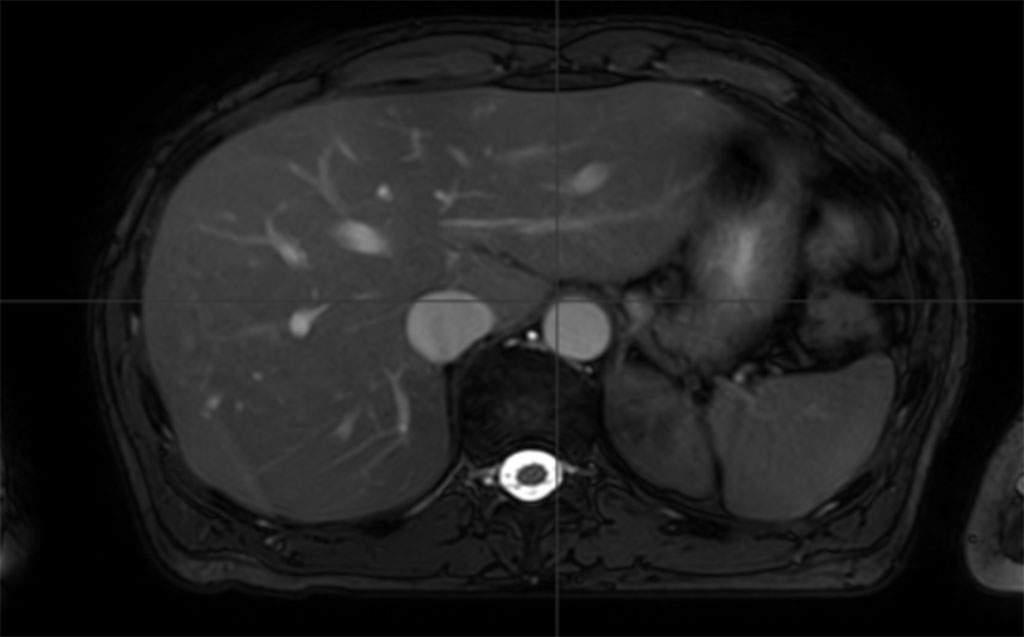

作为一个直线加速器塞皮尔知道“其他治疗”肯定包括放射治疗,她决心接受最好的治疗。在英格兰克劳利的办公室里,她在伊斯坦布尔的母亲家附近找到了一家诊所。当时的计划是,在塞尔皮尔接受巴塞利夫勒纪念医院的治疗时Elekta Versa高清™ 直线加速器她的母亲会帮助孩子们。塞皮尔的丈夫打算每隔几周从英国飞一次,和家人在一起。但是Covid-19提醒她事情并不总是按计划进行。